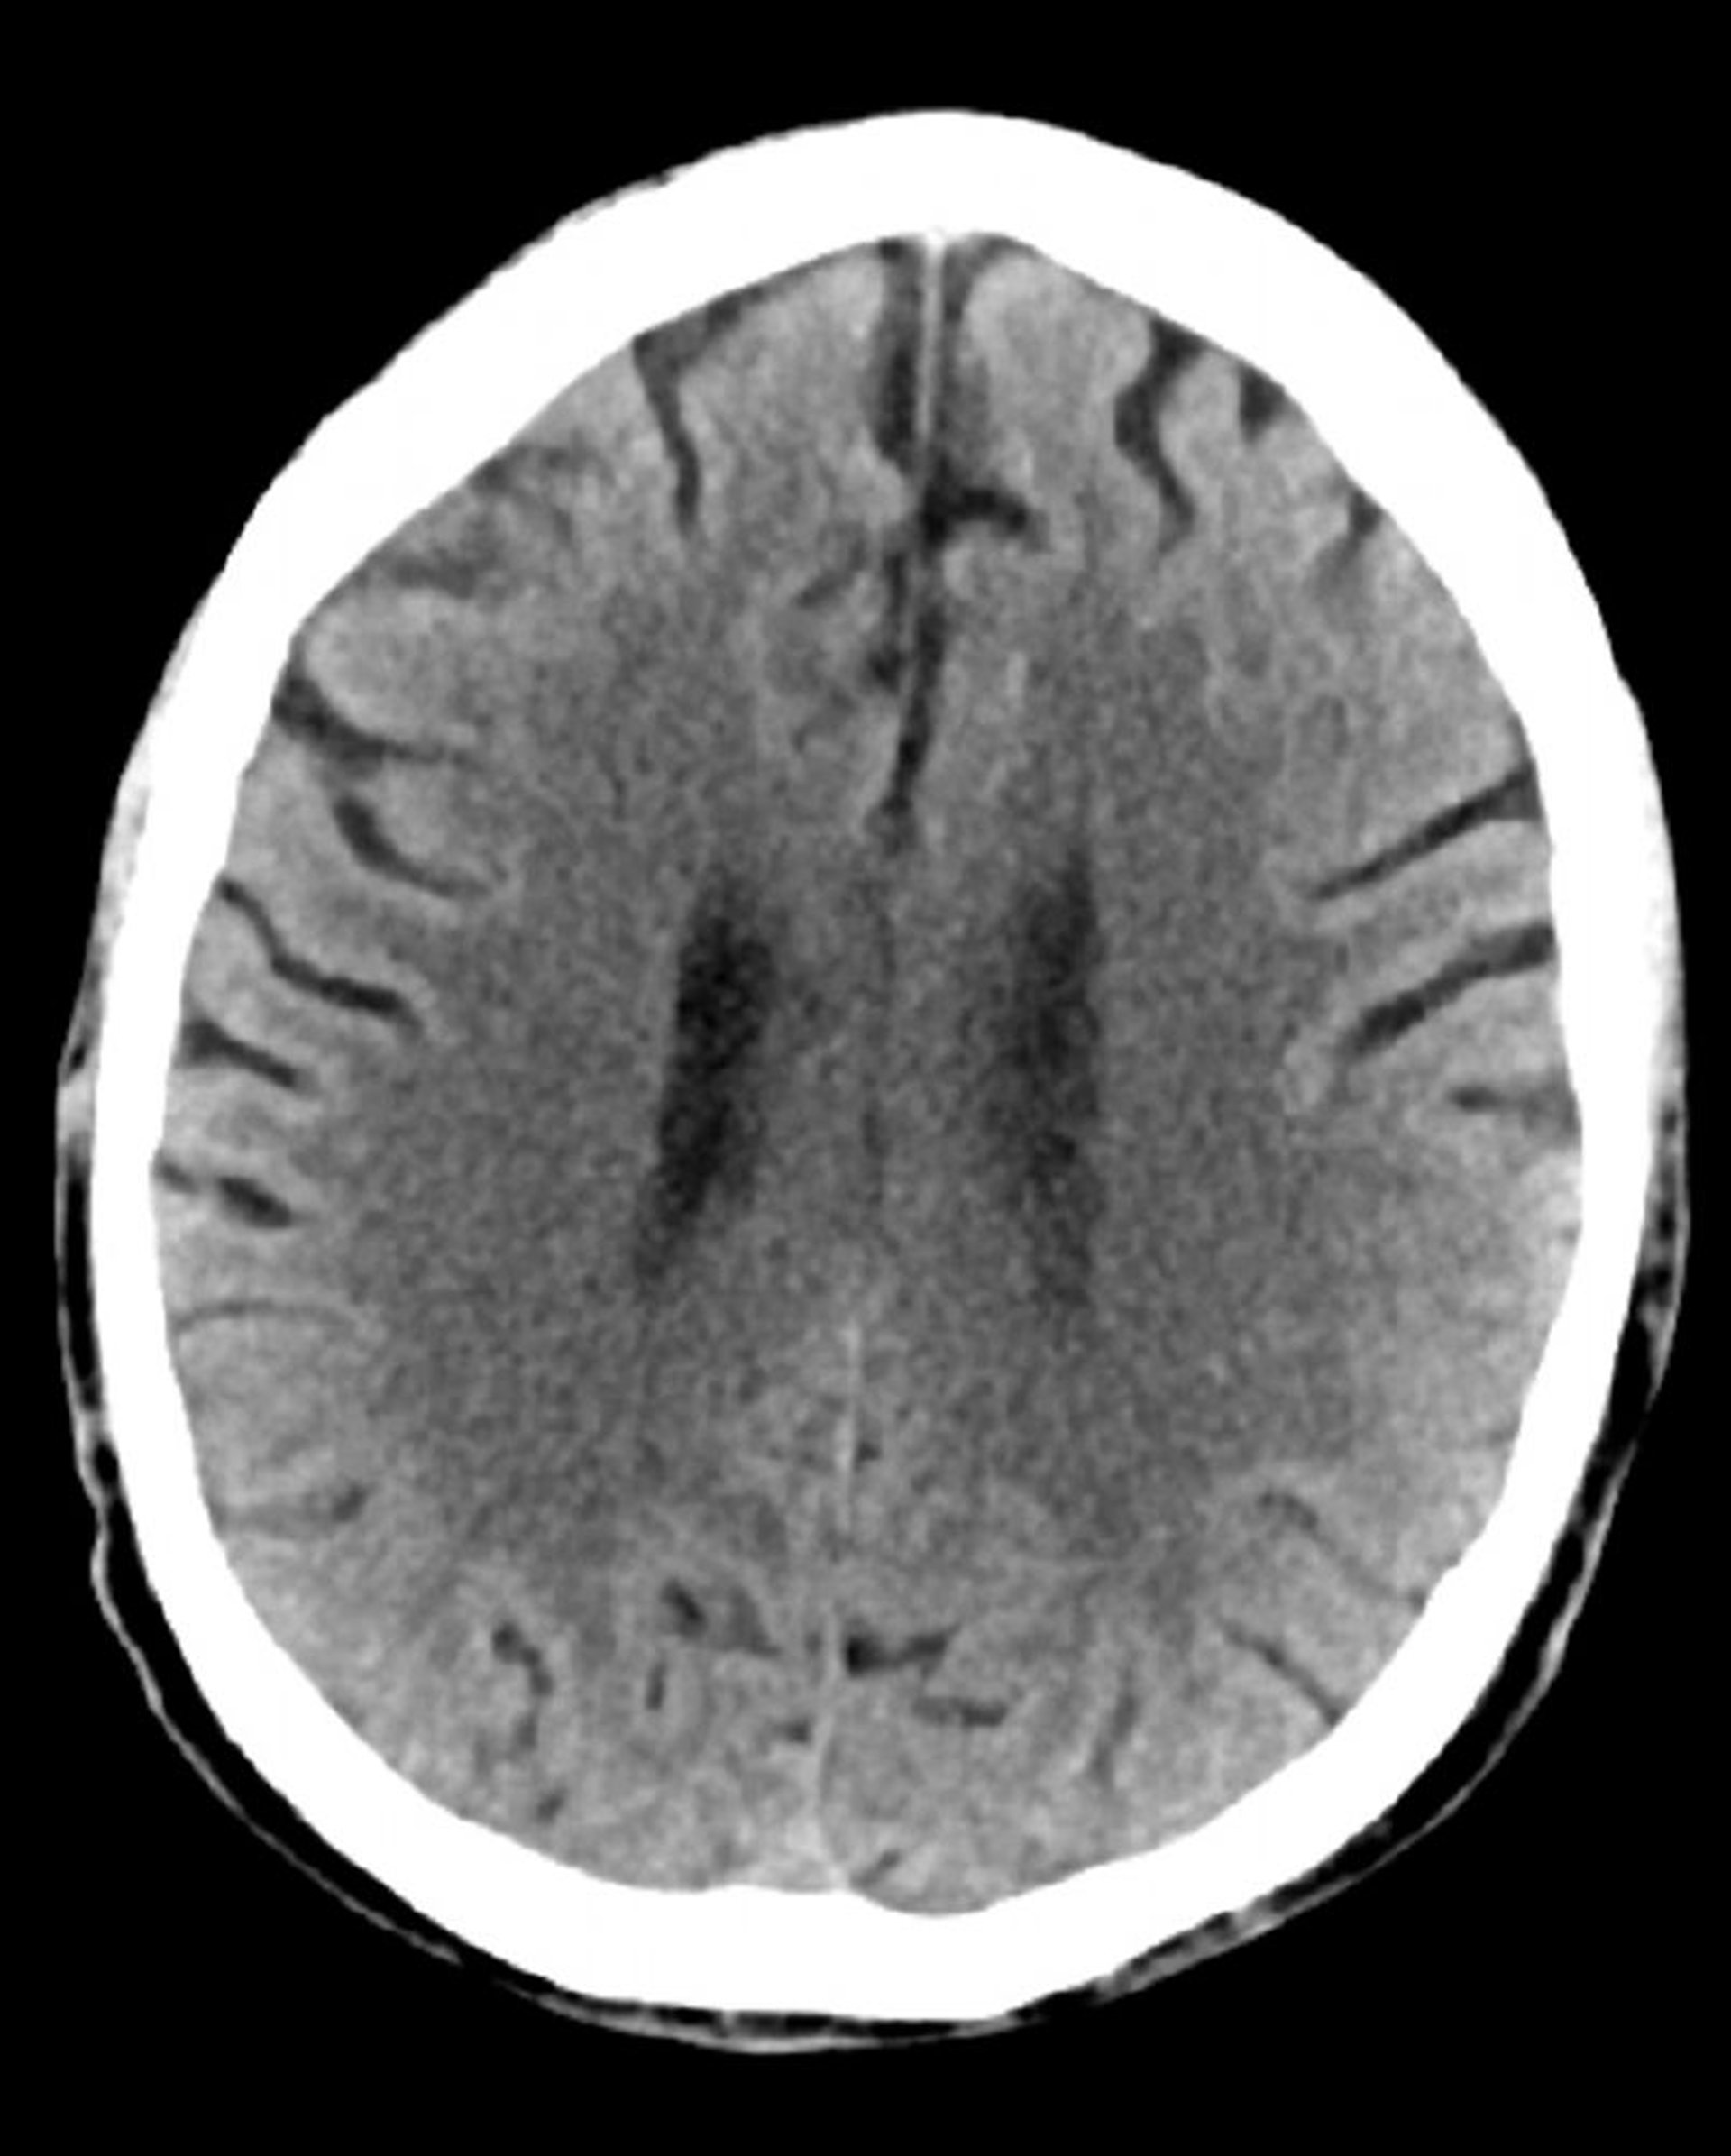

Tomografía computarizada craneal normal (adulto, 74 años)–diapositiva 3

Esta imagen es una tomografía computarizada craneal normal correspondiente a un adulto de 74 años. Cuando se compara con la tomografía computarizada craneal normal del adulto de 30 años de edad, se observa que los ventrículos y los sulcos son más grandes. Estos son hallazgos normales en este grupo de edad.